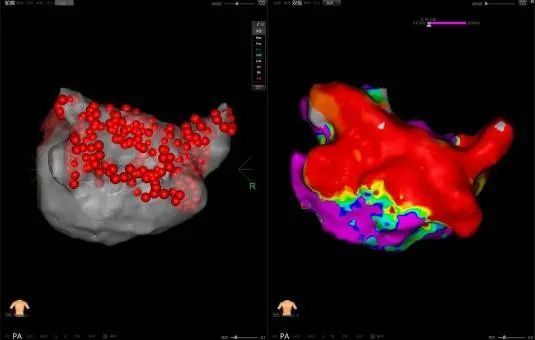

PFA是一種創(chuàng)新且有前景的微創(chuàng)、安全和高效的新興治療方法,通過瞬時(shí)的高電壓脈沖電場直接作用于心肌細(xì)胞,以不可逆電穿孔機(jī)制消融心臟組織,有效的隔絕異常激動及異位傳導(dǎo)路徑,從而恢復(fù)正常心律。PFA具有獨(dú)特的消融組織選擇性、消融時(shí)間極短、無熱損傷炎性水腫和附帶周圍組織損傷并發(fā)癥等特點(diǎn),是現(xiàn)有技術(shù)中針對心律失常更理想的消融手段,可大大減少因傳統(tǒng)消融存在手術(shù)并發(fā)癥風(fēng)險(xiǎn)及消融不足導(dǎo)致房顫復(fù)發(fā)的風(fēng)險(xiǎn)。與傳統(tǒng)的射頻導(dǎo)管消融或冷凍球囊消融相比,脈沖電場消融手術(shù)具有更加安全、消融效率高、并發(fā)癥少等諸多優(yōu)點(diǎn),徹底改變了房顫治療的格局,為房顫患者帶來更好的治療方案,帶來更多治愈的希望。

此次手術(shù)患者均為持續(xù)性房顫患者,由延安大學(xué)咸陽醫(yī)院吳棟梁院長、心律失常專家劉雄濤副院長帶領(lǐng)介入團(tuán)隊(duì)開展,安全高效、圓滿完成手術(shù),手術(shù)過程患者全程清醒,術(shù)中自訴感覺良好,無痛苦感受。術(shù)后患者的心律恢復(fù)并維持了竇律,目前恢復(fù)情況良好,無任何并發(fā)癥出現(xiàn)。